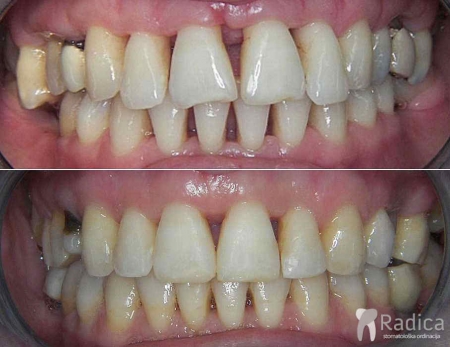

U sljedećem primjeru je fiksna ortodontska terapija rađena samo u donjoj čeljusti. Nakon toga su napravljeni novi protetski radovi u gornjoj i donjoj čeljusti – rad dr. Gorana Radice.

Na sljedećoj slici se mogu vidjeti početak i kraj ortodontske i protetske terapije. Protetske radove radio je dr. Goran Radica.